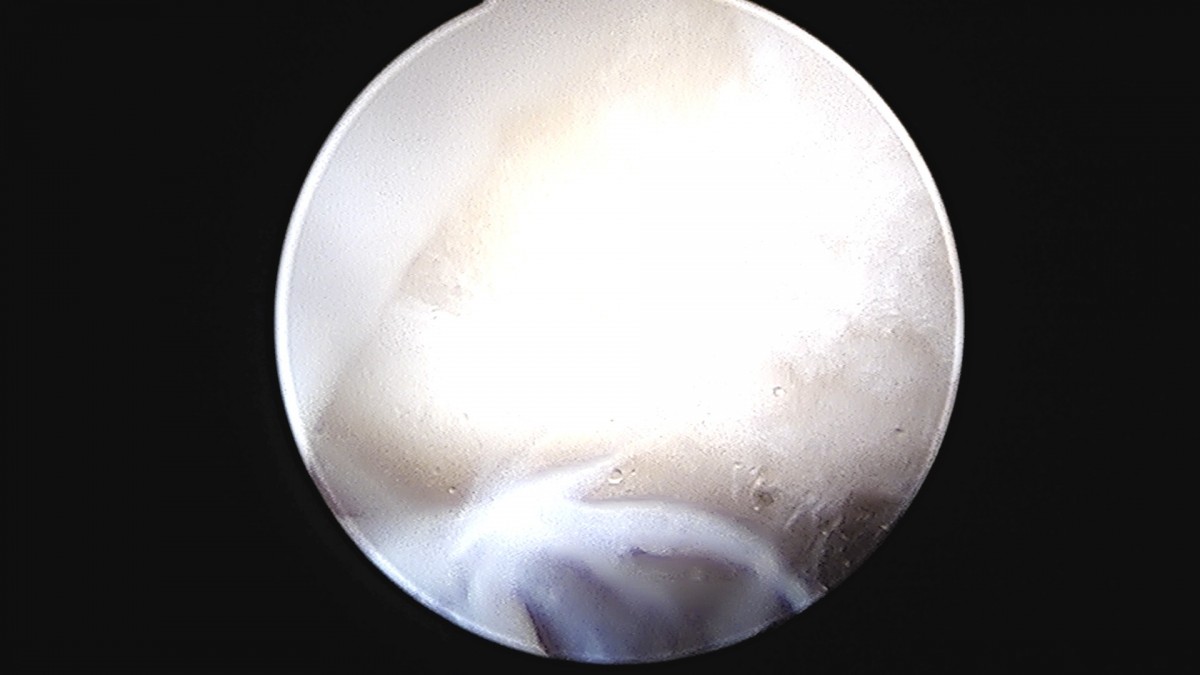

정지영원장님 발목 변연절제술 권공O 환자

dae765e4d9ac96aee867c9d6292d8784_1758009855_6748.jpg